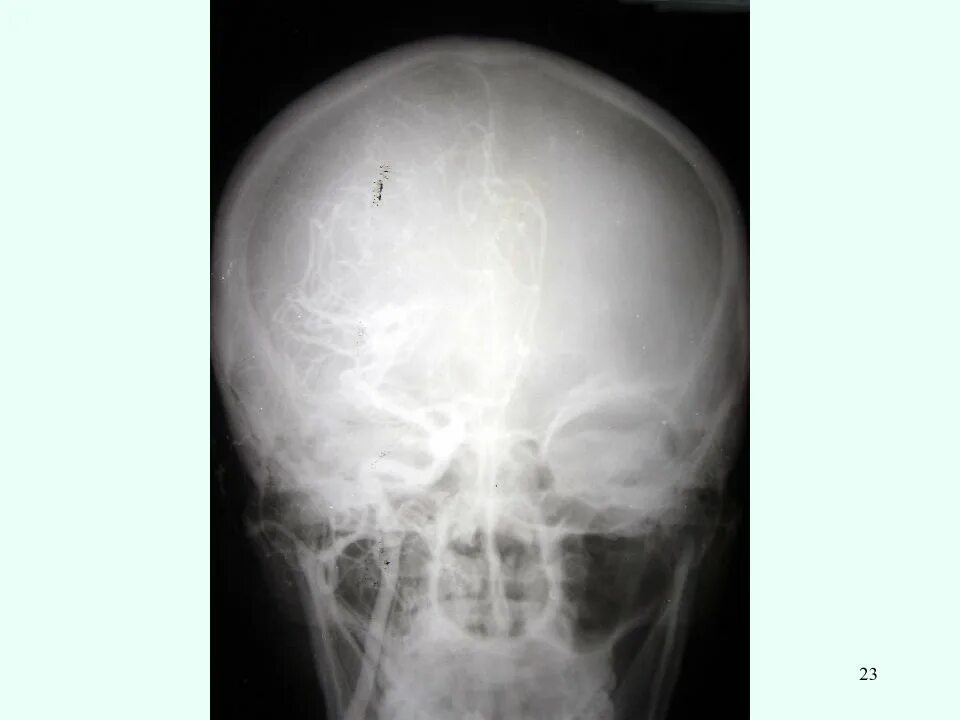

Зчмт сотрясение головного мозга